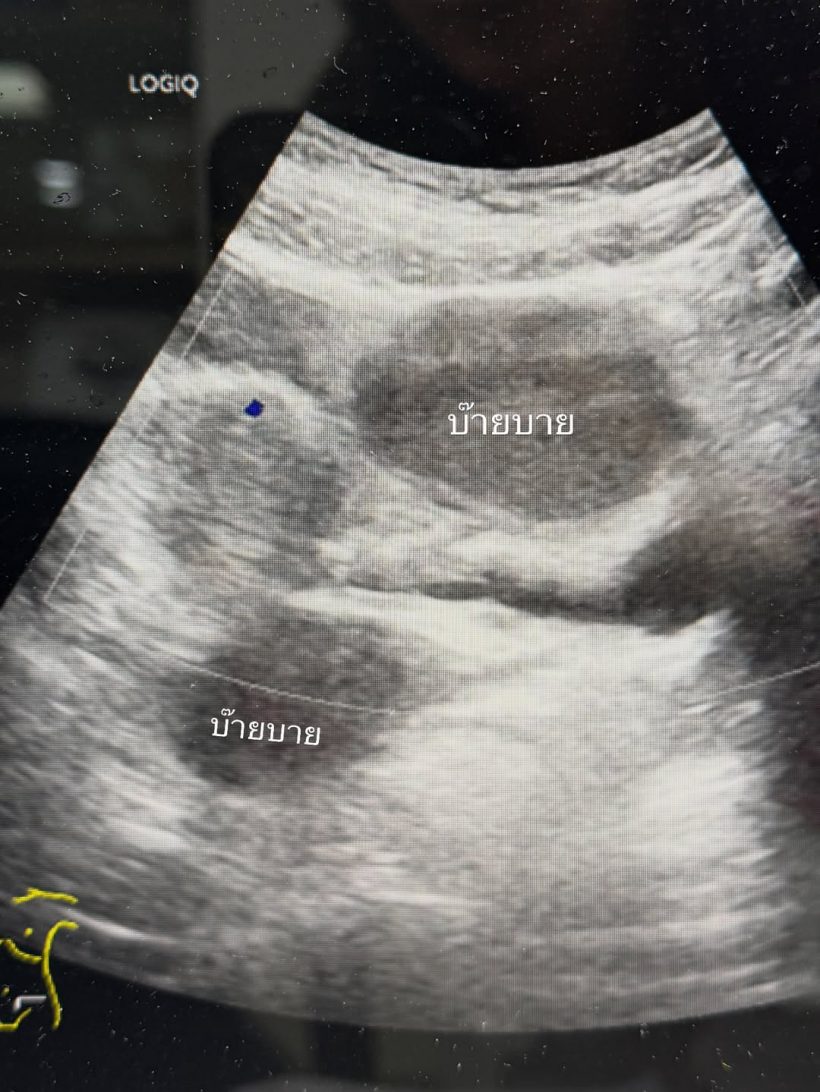

จ๊ะจ๋าต้องเข้ารพครั้งนี้เพราะอัลตร้าซาวน์เจอช็อกโกแลตซีสต์ 2 ลูกค่ะ น้องเป็นถุงน้ำรังไข่ที่เกิดจากเยื่อบุโพรงมดลูกเจริญผิดที่ ซึ่งถุงน้ำของจ๋ามีขนาดใหญ่เกินกว่าที่จะกินยาให้เค้ายุบได้ เลยต้องผ่าตัดออก ยังโชคดีที่ไม่ใหญ่มากไปจนต้องผ่าเปิดหน้าท้อง ใช้วิธีการส่องกล้องได้ ซึ่งแน่นอนเจ็บน้อยกว่า และแผลเล็กกว่า